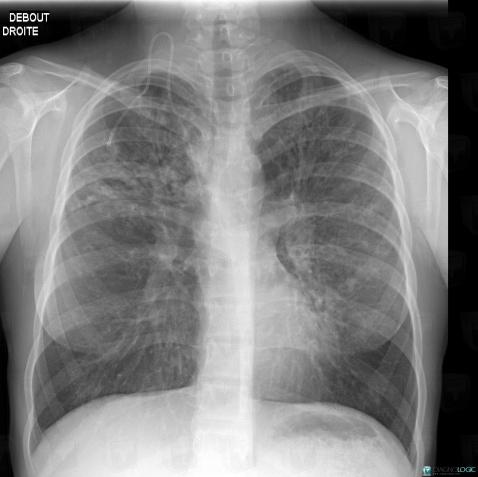

Mucoviscidose, Parenchyme pulmonaire, Voies aériennes, Radio

Voici les informations spécifiques à l'image clé ci dessus:

- Diagnostic Mucoviscidose, Localisation(s) Parenchyme pulmonaire, comportant les gammes Maladie prédominant dans les régions supérieures du poumonVoies aériennes, comportant les gammes